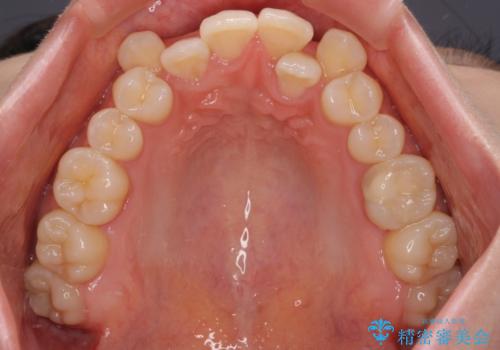

- 八重歯が気になるとのことで来院された患者様です。

上顎前歯部はデコボコが強く、歯を並べるためのスペースが不足しているため、左右の第一小臼歯を抜歯することとしました。

補助装置を併用したおかげで、出っ歯になることなくスムーズに治療を終えることができました。